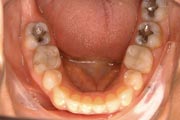

Crowding

Before